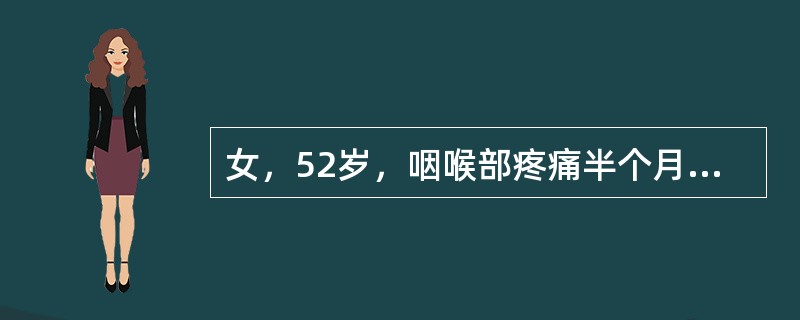

女,52岁,咽喉部疼痛半个月,伴低热,CT如图所示,可能诊断为()

A.咽旁脓肿

B.咽部神经鞘瘤

C.鼻咽血管纤维瘤

D.咽旁淋巴瘤

E.咽旁转移癌

[单选题]女,52岁,咽喉部疼痛半个月,伴低热,CT如图所示,最可能的诊断是()A.咽旁脓肿B.咽部神经鞘瘤C.鼻咽纤维血管瘤D.咽旁淋巴瘤E.咽旁转移瘤

[单选题,A2型题,A1/A2型题] 女,52岁,咽喉部疼痛半个月,伴低热,CT如图所示,可能诊断为()。A . 咽旁脓肿B . 咽部神经鞘瘤C . 鼻咽血管纤维瘤D . 咽旁淋巴瘤E . 咽旁转移癌

[单选题]女,52岁,咽喉部疼痛半个月,伴低热,CT如图所示,可能诊断为()A .咽旁脓肿B .咽部神经鞘瘤C .鼻咽血管纤维瘤D .咽旁淋巴瘤E .咽旁转移癌

[单选题]女,52岁,咽喉部疼痛半个月,伴低热,CT如图所示,可能诊断为()A . 咽旁脓肿B . 咽部神经鞘瘤C . 鼻咽血管纤维瘤D . 咽旁淋巴瘤E . 咽旁转移癌

[单选题]女,52岁,咽喉部疼痛半个月,伴低热,CT如图所示,最可能的诊断是()A . 咽旁脓肿B . 咽部神经鞘瘤C . 鼻咽纤维血管瘤D . 咽旁淋巴瘤E . 咽旁转移瘤